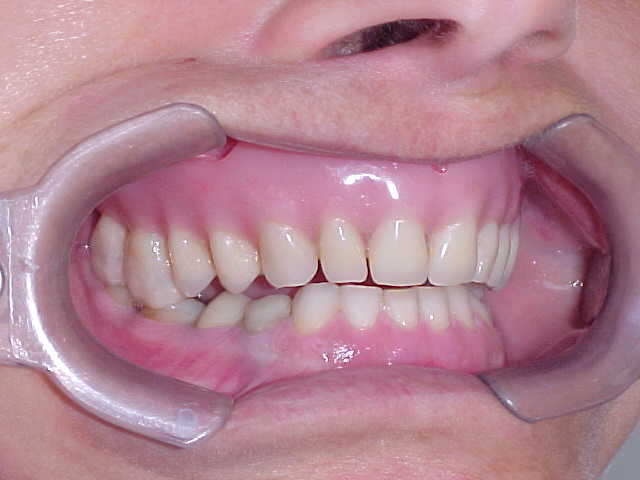

Diagnóstico preliminar das principais ocorrências: Prótese total na maxila em articulação com dentição natural inferior, apresentando acentuado trespasse horizontal (mordida profunda) e inclinações linguais generalizadas, com ausência do primeiro molar inferior esquerdo.

Plano de tratamento: 1) Tratamento ortodôntico para a mandíbula, com o propósito de reverter (alinhar e nivelar) a má-oclusão descrita acima; 2) Implantes maxilares como base de sustentação de prótese fixa, com gengiva artificial para compensar a reabsorção óssea ocorrida ao longo dos anos; 3) Reposicão do elemento ausente na mandíbula com implante e coroa metalo-cerâmica; 4) Próteses unitárias diversas sobre raízes naturais; 5) Reanatomizações e restaurações diversas em resina composta direta.

Confirmação da inclinação lingual generalizada em todos os elementos dentários